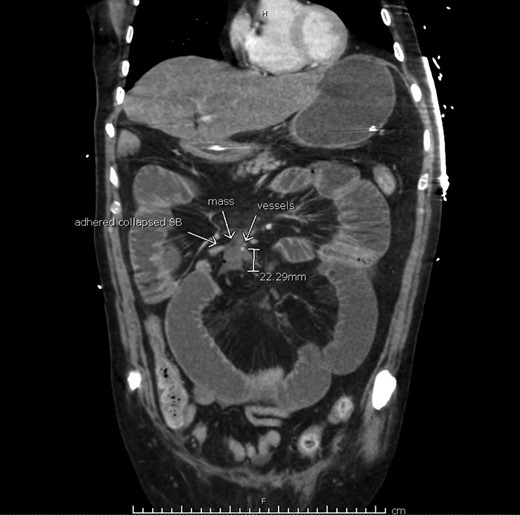

A computed tomography (CT) scan of the abdomen and pelvis was performed (Fig. 2), demonstrating a high-grade mechanical bowel obstruction with transition point in the mid abdomen adjacent to a mesenteric soft tissue mass, most likely in keeping with recurrence of the mesenteric B-cell lymphoma. There was interloop free fluid, mesenteric congestion and gas locules adjacent to the soft tissue mass—thought to represent mesenteric venous gas and bowel ischemia.

Computerized tomography suggesting tumor recurrence and small bowel obstruction.